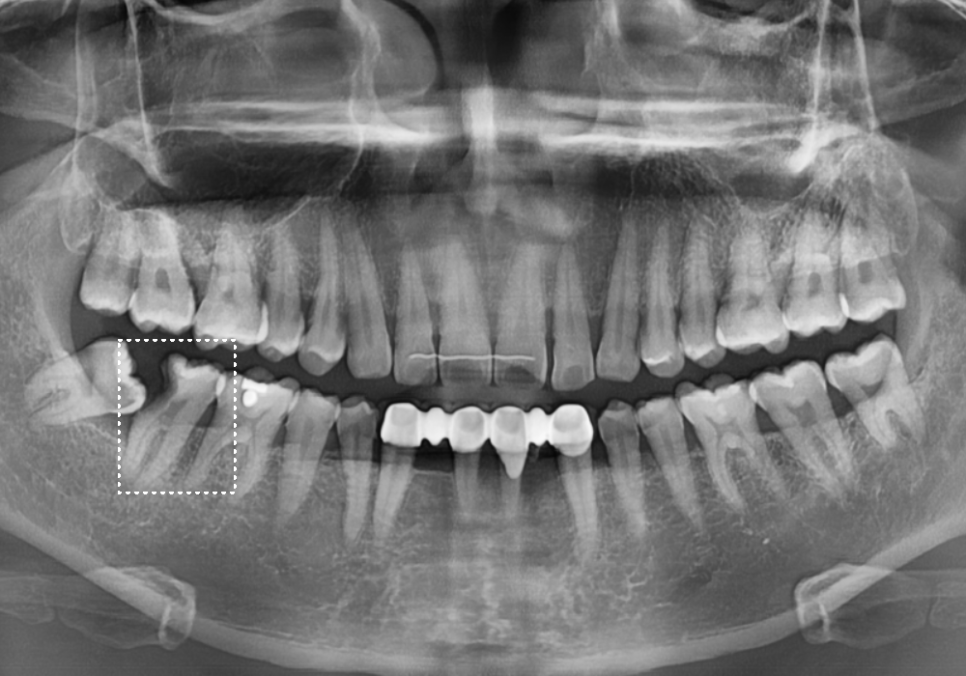

파노라마 사진을 분석해 보니,

환자분은 위아래 총 4개의 사랑니를

모두 가지고 계셨어요.

그런데 재밌는 것은

다른 3곳의 사랑니 주변은 아주 멀쩡한데,

유독 오른쪽 아래 사랑니만 유독

다른 모습으로 숨어 있다는 점인데요.

250523

사진을 보시면 확연한 차이가 느껴지시나요?

이렇게 혼자만 유난히 도드라져 보이는 이유는

바로 사랑니가 자라난 '방향' 때문입니다.

문제가 된 오른쪽 아래 사랑니(#48)는

다른 치아들처럼 곧게 난 게 아니라,

혼자 옆으로 툭 쓰러져 앞 치아의 허리 부분을

강하게 밀고 있는 '수평 매복' 상태였거든요.